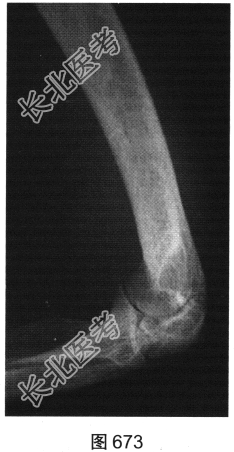

患者女性,62岁,右侧肘关节肿胀、疼痛1年余。肘关节正侧位X线片及CT检查见图673~图676。

- 多项选择题1.对该患者影像征象描述正确的是( )

A、关节腔积液

B、尺骨关节面囊状骨质破坏

C、肘关节面明显骨质增生硬化

D、肘关节软组织肿胀

E、尺骨近段骨膜反应

F、肘关节间隙变窄

G、骨质疏松